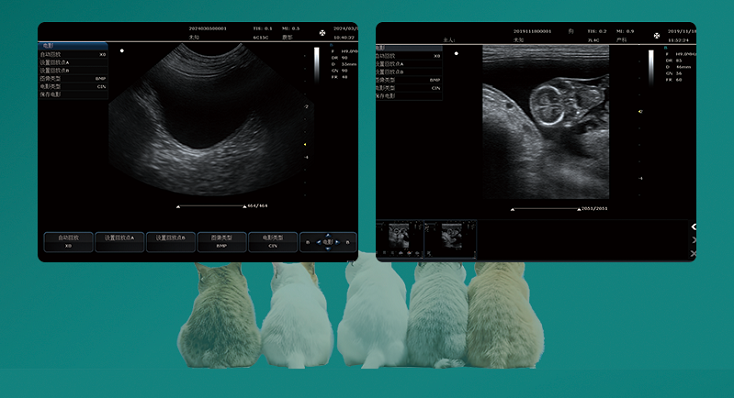

Convex Probe-B Mode-Uterus1 Pig

Convex Probe-B Mode-Uterus2 Pig

Linear Probe-B Mode- Pregnant 1 Cow